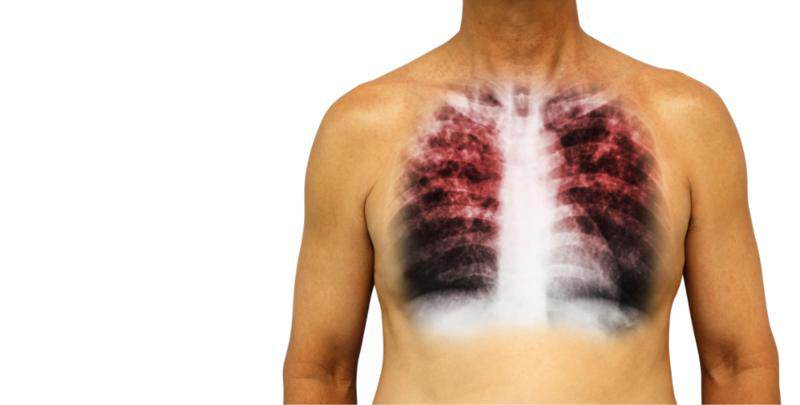

4.吸烟会严重损害青少年呼吸系统和心血管系统,并且会加速其成年后慢性病的发生;